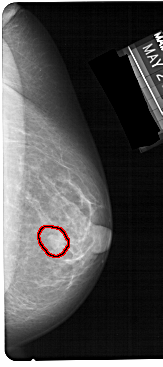

FILE: A_1304_1.RIGHT_CC.OVERLAY

TOTAL_ABNORMALITIES 1

ABNORMALITY 1

LESION_TYPE MASS SHAPE OVAL MARGINS CIRCUMSCRIBED

ASSESSMENT 4

SUBTLETY 4

PATHOLOGY BENIGN

TOTAL_OUTLINES 1

BOUNDARY